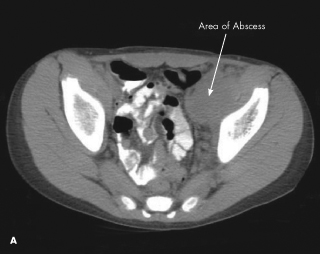

osteomyelitis

Brian T. Kloss, DO, JD, PA-C; Katherine Dougher, MD; Deepak M. Kamat, MD, PhD

<p class="p1"><img src="/sites/default/files/transfer/1208CFP_PCAbscess_A.jpg" width="90" height="90" style="float: left; margin:...